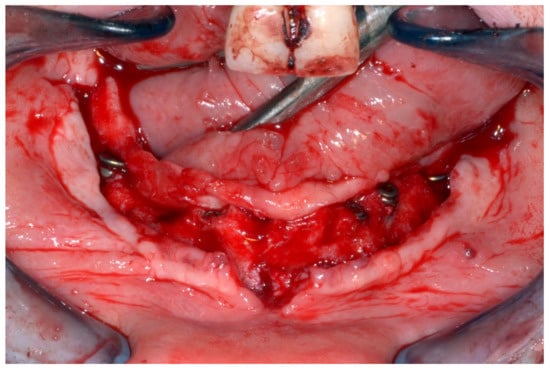

6.2.4. Intra-Operative Documentation:

In March 2013, twelve guided dental implants were placed at sites # 12, # 13, # 15, # 22, # 23, # 25, # 33, # 34, # 36, # 43, # 44, and # 46 (Figure 22, Figure 23, Figure 24, Figure 25 and Figure 26)

Figure 25.

Guided implant insertion.

Figure 26.

Mandibular implants in place.